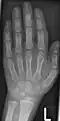

- Röntgenaufnahmen der Handknochen von Kindern unterschiedlichen Alters

-

Junge, 3,5 Jahre. Beachte auch die Brachymesophalangie am Kleinfinger -